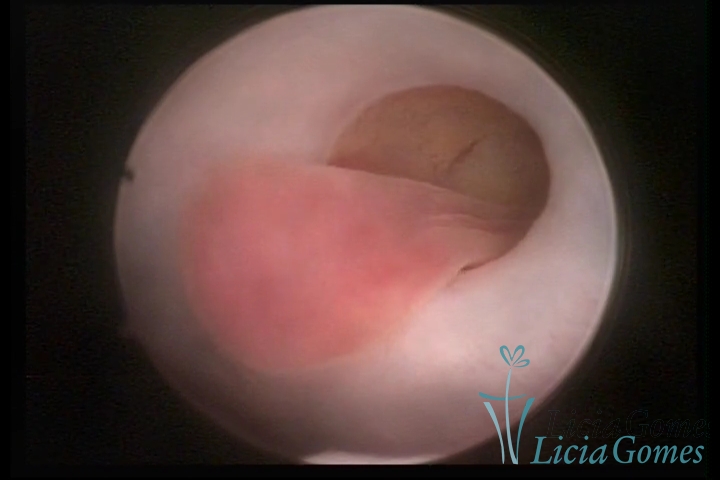

ENDOCERVICAL POLYPS

Benign tumors resulting from the reactive focal proliferation to inflammatory processes or hyperestrogenism situations, which may be sessile (with a large implantation) or stalked.